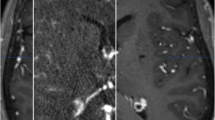

Image verification of the segmented thalamic nucleus. A T1 image (left), quantitative susceptibility map (QSM, middle), and paramagnetic susceptibility map (X_para, right) from patient 8. The upper image combines part of the segmented thalamic nucleus, and the lower image is the original image. The edge details for the thalamus are more visible in the X_para image compared with other images, especially in CMT (pointed out by the cross). B An enlarged view of the thalamic nucleus fused with the T1 image. The boundary of the segmented CMT is close to the result from the QSM. These images are from screenshots from 3D Slicer. CMT centromedian thalamic nucleus, MDm mediodorsal medial magnocellular, PuA pulvinar anterior, PuM pulvinar medial, VLp ventral lateral posterior, VPL ventral posterolateral

Target Location

Presently it is not possible to locate the CMT using the imaging landmarks provided by CT or MRI [15]. At present, many operations rely on atlas or empirical coordinates (posterior commissure and the plane level, ~ 10 mm away from the midline). Individual anatomical variation due to a congenital anomaly will lead to electrode misplacement. Unfortunately for patients with an anatomical variation, electrode displacement occurs [37]. Recently, some research has indicated that QSM and magnetization-prepared 2 rapid acquisition gradient echoes (MP2RAGE) are promising methods for improving the visualization of the CMT [12, 38]. These scanning and processing methods are complex and need further verification. Especially in QSM images, although the CMT is visible, it is difficult to distinguish the boundary, as it yields a low signal (Fig. 3).